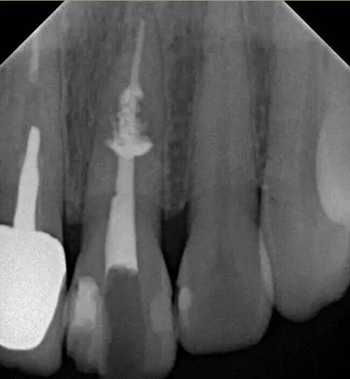

診斷:左上中切牙牙根內(nèi)吸收。治療計劃:左上中切牙根管治療,全冠修復(fù)。 治療過程:患者知情同意。使用含1/100,000腎上腺素的4%鹽酸阿替卡因(碧蘭麻,艾龍)局部浸潤麻醉,橡皮障隔濕。去腐未盡露髓,露髓孔出血多。開髓,使用10#不銹鋼K銼(MANI,日本)探查根管,根管中段有鈣化物阻擋,不能達到牙根全長(圖3A)。在顯微鏡下(Leica M400E,萊卡, 德國) 使用超聲尖(E1根管治療超聲尖,啄木鳥公司,中國)通開,采用根管長度測量儀(Root ZX, Morita公司,日本)加診斷絲片法(圖1B)測量根管長22 mm。使用控制扭矩馬達(X-smart,登士柏)和鎳鈦旋轉(zhuǎn)器械(Hero 642, Micromega)根管預(yù)備,根管預(yù)備過程中使用5.25%次氯酸鈉溶液沖洗。 根備完成后使用超聲蕩洗根管,5.25%次氯酸鈉溶液3 分鐘, 17% EDTA溶液1分鐘。干燥根管,使用螺旋充填器根管內(nèi)封氫氧化鈣糊,氧化鋅丁香油水門汀暫封。1周后患者復(fù)診,患者述無術(shù)后不適,檢查暫封完好,無叩痛,不松,牙齦無紅腫瘺管。使用橡皮障隔濕,去除暫封物,超聲蕩洗根管,5.25%次氯酸鈉溶液3 分鐘, 17% EDTA溶液1分鐘。干燥根管,牙膠尖(達雅鼎,中國)和必蘭根充糊劑(Cortisomol, 艾龍公司,法國)熱垂直加壓法根管充填。術(shù)后片顯示根充恰填,可見牙膠/糊劑被壓入鈣化物周圍和內(nèi)部縫隙內(nèi)